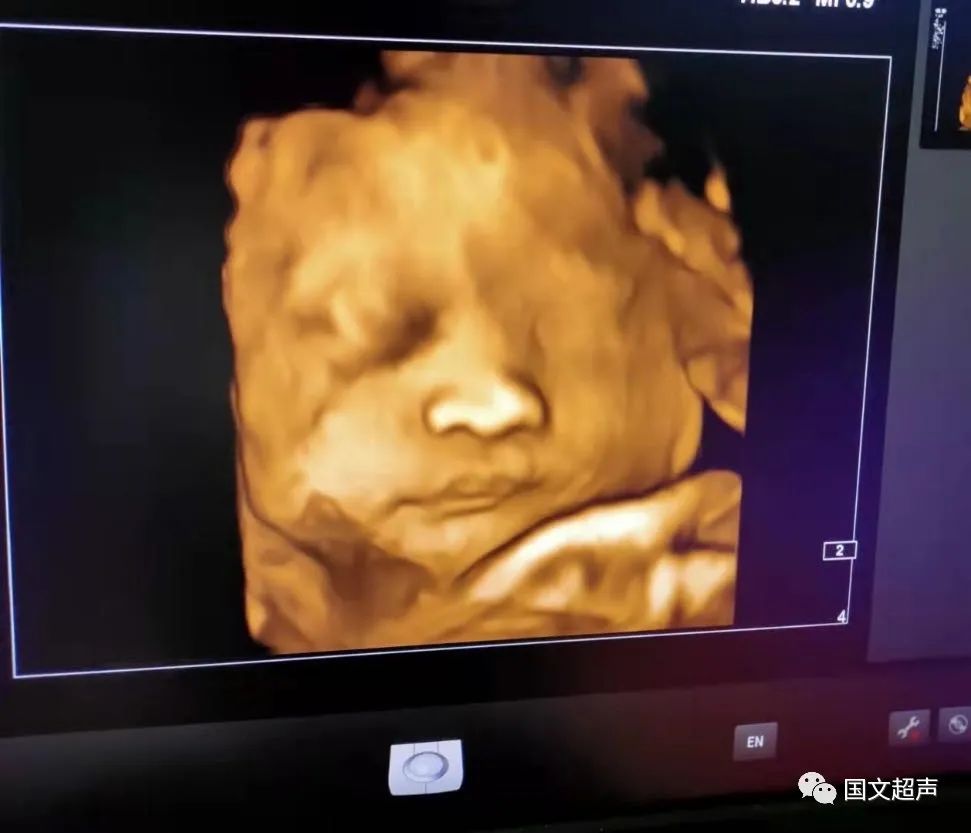

一.飛利浦EPIQ7高端四維彩超

我院目前使用的是飛利浦EPIQ7高端四維彩超,它擁有高品質(zhì)自動(dòng)成像分析技術(shù),分辨率及清晰度高,可以較清晰的顯示宮內(nèi)胎兒的生長(zhǎng)發(fā)育情況,為診斷胎兒先天性畸形,如唇裂、脊柱裂、顱腦發(fā)育異常、骨骼發(fā)育異常、心血管畸形等提供準(zhǔn)確的科學(xué)依據(jù)。